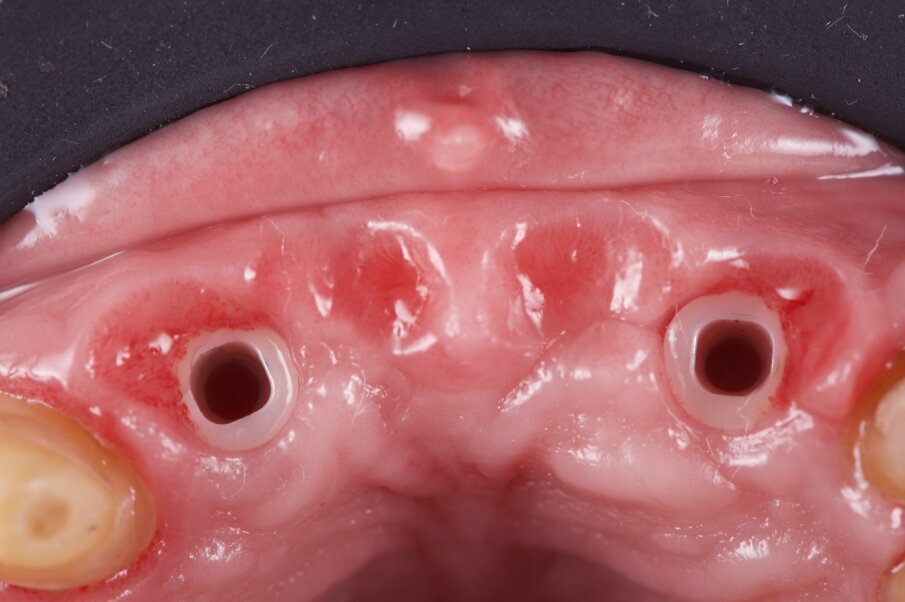

La rigenerazione ossea è stata ottenuta secondo l’impiego di biomateriale di origine bovina demineralizzato e stabilizzato con una membrana a lento riassorbimento in pericardio nativo fissata con dei chiodini in titanio (Fig. 23). Com’è noto la stabilità dell’innesto è un requisito indispensabile per ottenere una reale rigenerazione ossea stabile nel tempo. Dopo 4-6 mesi si effettua una radiografia di controllo eseguendo successivamente un opercolo perimplantare. In questo caso data la lieve deiscenza presente si è optato per l’impiego di un diatermocoagulatore per limitare il danno biologico ai tessuti limitrofi e mantenere inalterata la rivascolarizzazione della sede, inoltre non essendo un materiale metallico ma bensì ceramico, l’eventuale contatto viene disperso e non assorbito dall’impianto (Fig. 24). Data l’ottima stabilizzazione funzionale e volendo contenere i costi viene realizzata un’impronta digitale dell’arcata col primo provvisorio in situ e alla sua rimozione un’impronta dell’intera arcata con e senza gli scan body implantari (Fig. 25). Per mantenere l’opercolo ottenuto si utilizzano delle cappette di guarigione sempre in Zirconia che serviranno anche per stabilizzare i tessuti perimplantari (Fig. 26).

Fig. 25_Dopo opercolarizzazione si provvede a rilevare l’impronta con appositi transfer che per le impronte digitali si chiamano scan body e si differenziano per il tipo di impianto e per il tipo di scanner intraorale utilizzato.

Fig. 26_Al termine dell’impronta si posizionano delle cappette di guarigione in zirconia in grado di stabilizzare il tessuto gengivale.